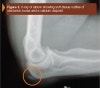

X-ray : 주두 점액낭염(Olecranon bursitis)